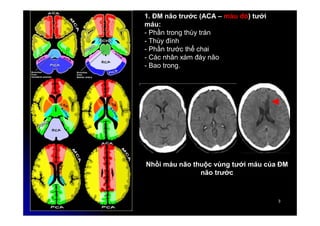

1. ĐM não trước (ACA – màu đỏ) tưới

máu:

- Phần trong thùy trán

- Thùy đính

- Phần trước thể chai

- Các nhân xám đáy não

- Bao trong.

Nhồi máu não thuộc vùng tưới máu của ĐM

não trước